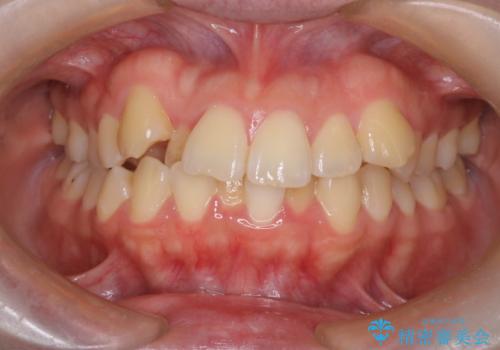

【ワイヤー矯正】八重歯 歯のでこぼこを治したい!